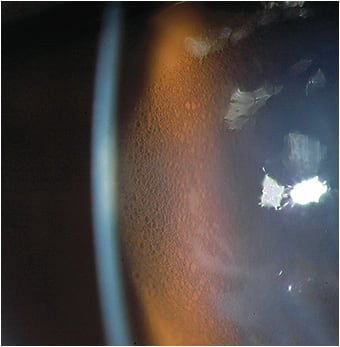

Therefore, whenever epithelial corneal edema is observed—aside from a careful evaluation of the lens fit (more on this below) to determine whether there is adequate alignment, no lens suction from a very tight lens or crowding at the limbal region, an adequate Dk/t in the lens system, and/or tear exchange—it is imperative to always check the IOP; all that may be needed is to properly manage and lower the IOP (Figure 2).